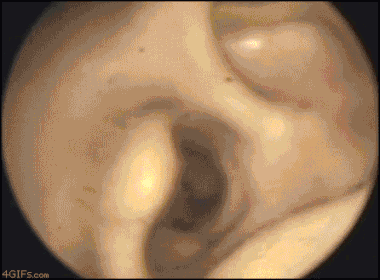

Khi nghe thấy tiếng động kỳ lạ trong tai mình, rất có thể bạn đã "được" một con vật nhỏ nào đó thăm hỏi.